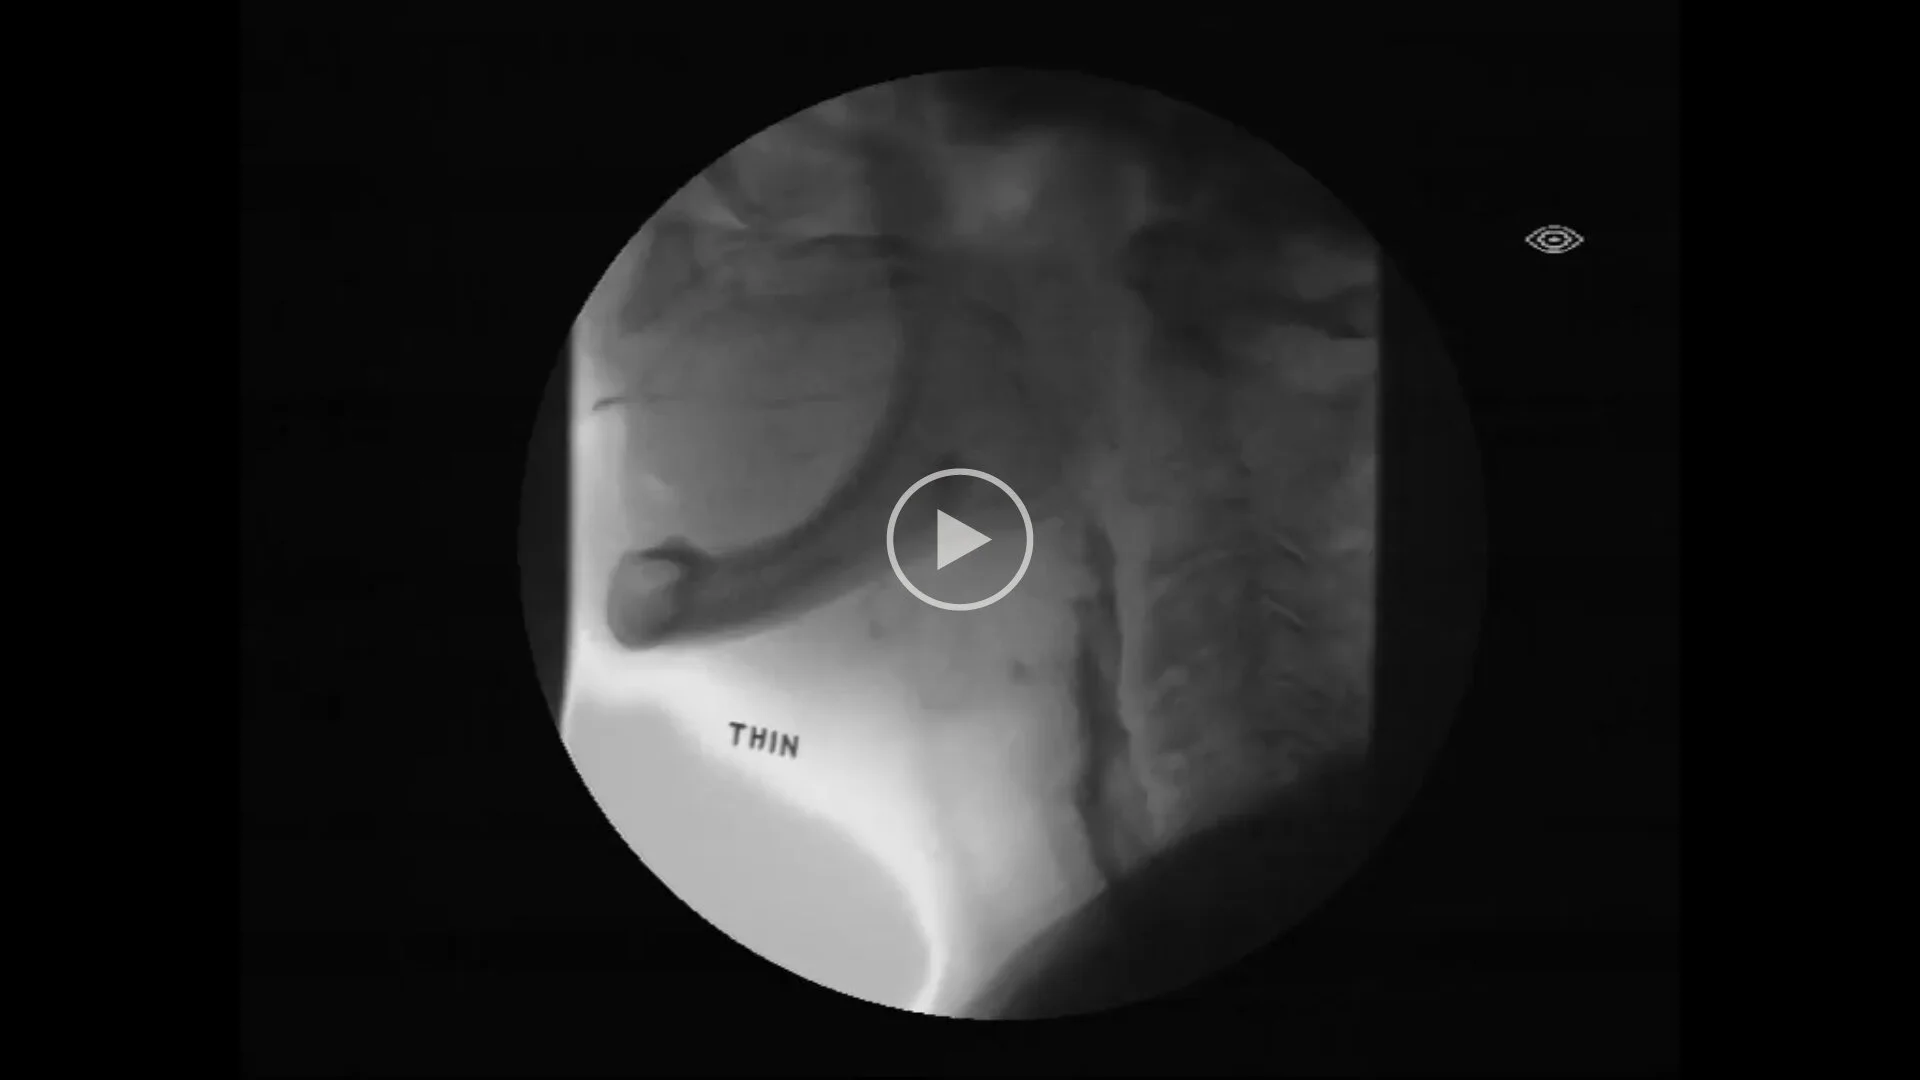

Videofluoroscopic Swallowing Study (VFSS / MBS) –

Best-practice assessments for swallowing

The best way to assess swallowing difficulties is with a Videofluoroscopic Swallowing Study (VFSS) assessment, also known as Modified Barium Swallow (MBS). This test assesses swallowing with a dynamic x-ray in real-time, with a range of food and fluids mixed with barium – a safe, ingestible metallic compound that makes food and fluids easier to see on xrays. Barium is not harmful, and the x-ray machine is only turned on while you swallow. No specific fasting is required.

Find out more about VFSS/MBS in this short video

Watch Video